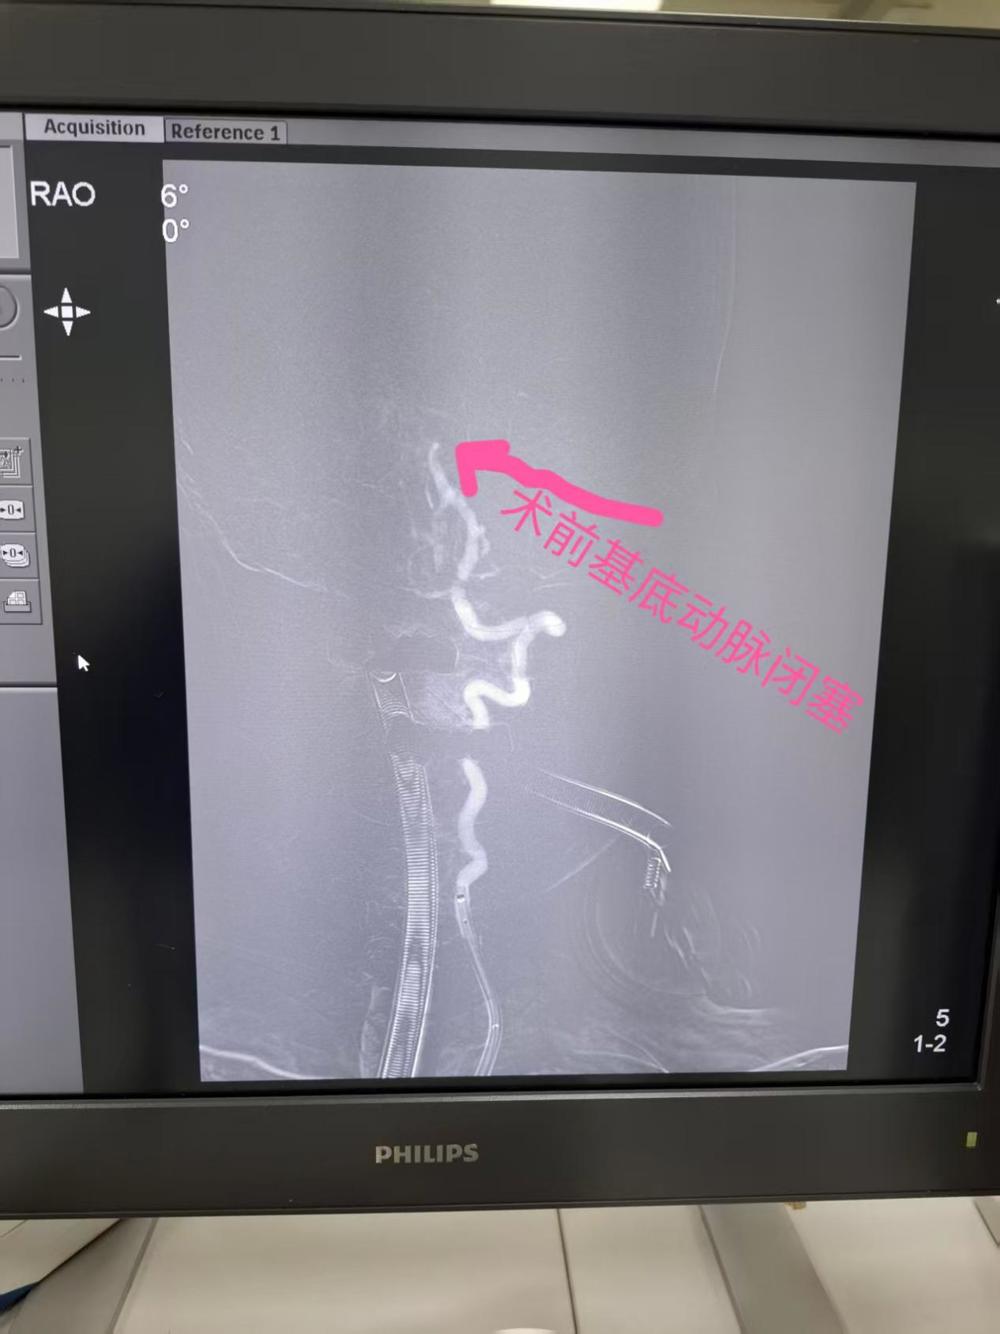

近日,63岁的黄先生入院前3天出现头晕,在诊所治疗,入院前3小时病情加重,出现左侧肢体乏力,言语不清。入院前30分钟病情继续加重,出现昏迷不醒,家属意识到疾病的危险,这很有可能就是“中风”的表现,马上送至我院急诊科就诊。急诊科医师接诊后考虑脑卒中,立刻为黄先生开通了卒中绿色通道,通知神经内科值班医师前来急会诊,神经内科医师经过查看病病人结合头颅MRI检查考虑黄先生基底动脉闭塞,脑桥梗死。立即通知神经内科主任、副主任医师胡华林指导治疗。胡华林主任会诊后将脑血管取栓手术的必要性与风险详细告知家属,征得同意后急诊进行手术治疗。

神经内科胡华林主任及其介入团队快速制定手术方案。通过介入取栓加脑血管球囊扩张成形手术,成功开通了闭塞的基底动脉,从穿刺到基底动脉首通时间为20分钟,黄先生的基底动脉成功恢复了血流再通。手术非常顺利,黄先生术后言语恢复清晰,能够自由下床活动,基本完全恢复正常。